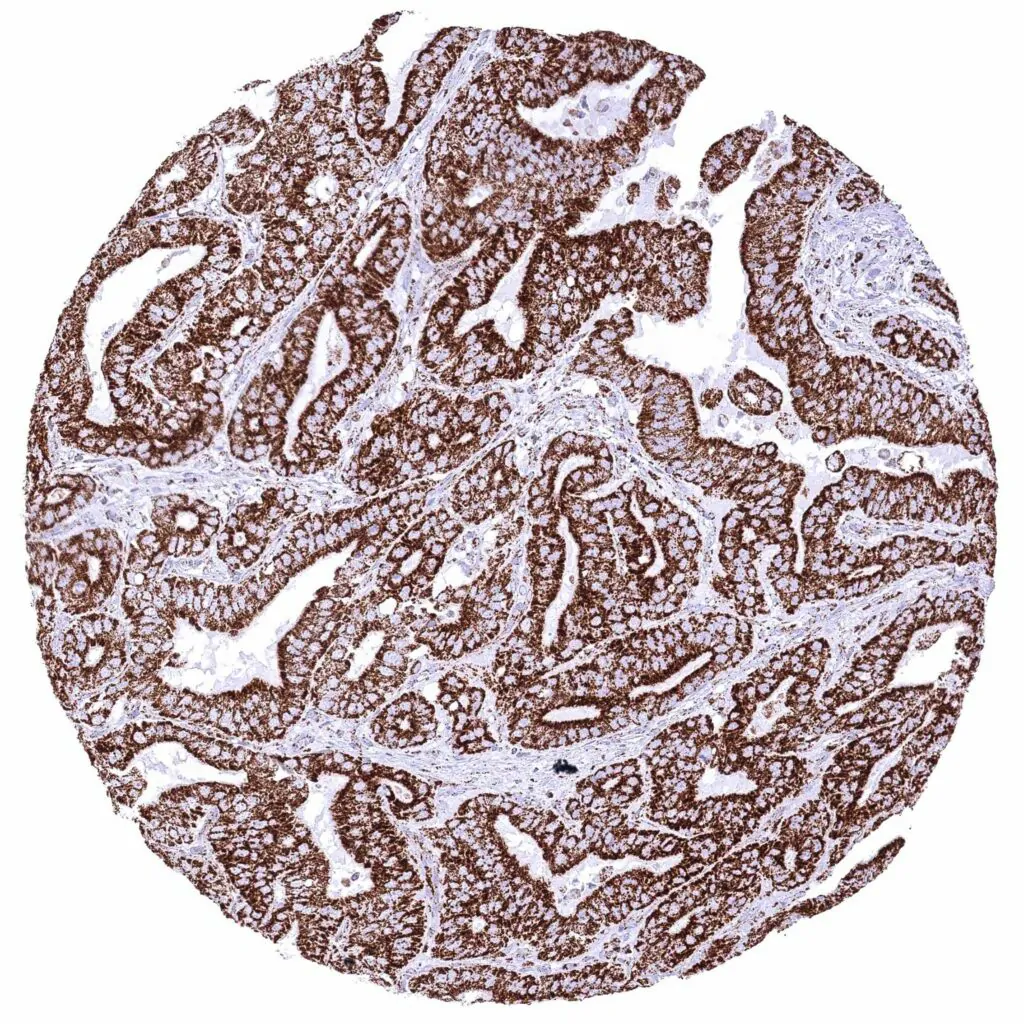

Colon – Colorectal adenocarcinoma with strong cytoplasmic ATP5J staining of all tumor cells.